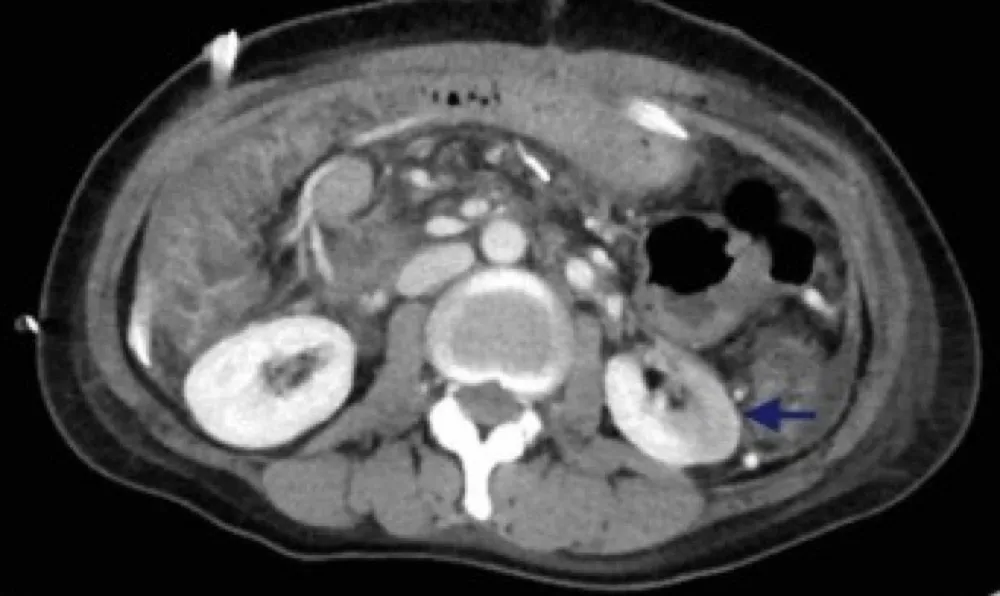

Paciente de 40 anos se apresenta com piora de hipertensão de início recente, há quatro meses ela havia sido submetida à duodenopancreatectomia devido neoplasia pancreática. O rim esquerdo necessitou de deslocamento manual para facilitar a remoção do tumor e otimizar a radioterapia. Uma tomografia computadorizada pós-cirúrgica mostrou uma área ampla de hipoperfusão segmentar na face inferior do rim esquerdo (Fig. 1, seta).

Realizado investigação da atividade de renina plasmática e do nível sérico de aldosterona que foram 8,4 ng/mL por hora e 18 ng/dL, respectivamente. O uso de losartana normalizou a pressão arterial. Imagens subsequentes mostraram evolução para atrofia cortical do parênquima previamente isquêmico (Fig. 1C, seta). Após vários meses, sua pressão arterial voltou ao normal; a losartana foi descontinuada.

(A) Uma tomografia computadorizada pré-procedimento do abdômen e pelve com contraste intravenoso com rins simétricos (seta). (B) Tomografia computadorizada do 6º dia pós-cirúrgico com uma nova região se hiporealce na região inferior polo do rim esquerdo consistente com hipoperfusão/infarto renal (seta). (C) Tomografia computadorizada 5 meses após a cirurgia com atrofia focal do polo inferior do rim esquerdo (seta).